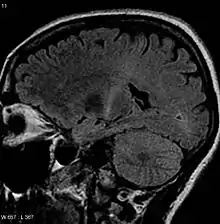

Because symptoms of ALS can be similar to those of a wide variety of other, more treatable diseases or disorders, appropriate tests must be conducted to exclude the possibility of other conditions. One of these tests is electromyography (EMG), a special recording technique that detects electrical activity in muscles. Certain EMG findings can support the diagnosis of ALS. Another common test measures nerve conduction velocity (NCV).[89] Specific abnormalities in the NCV results may suggest, for example, that the person has a form of peripheral neuropathy (damage to peripheral nerves) or myopathy (muscle disease) rather than ALS. While a magnetic resonance imaging (MRI) is often normal in people with early-stage ALS, it can reveal evidence of other problems that may be causing the symptoms, such as a spinal cord tumor, multiple sclerosis, a herniated disc in the neck, syringomyelia, or cervical spondylosis.[3][90]